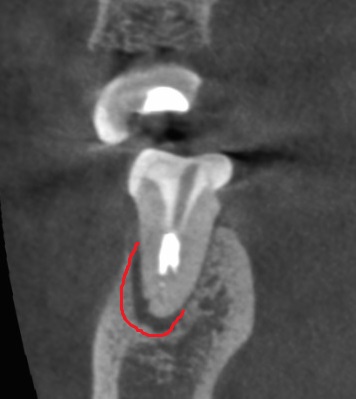

CT検査をすると、

左下6番目の歯(右から2番目)の根っこの先が黒くなっています。

赤い枠のココです。

(手前の5番目の歯も黒くなっていますが、

特に症状がないので今回は治療はしてません(^^;)

細菌により膿がたまって、根の先の骨が溶けて黒く見えています。